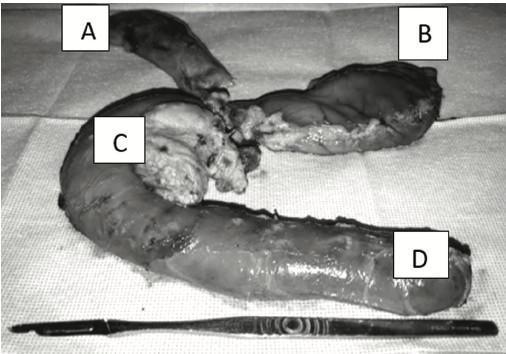

El procedimiento de Whipple es considerado como unos de los mas complejos y desafiantes, ya que se debe rea- lizar una resección en bloque, con la reconstrucción bi- liar, pancreática y del tránsito gástrico posterior (Figura

1); la mortalidad reportada en las mejores series es del 1-3%. Sin embargo, las complicaciones postoperatorias continúan siendo elevadas alcanzando el 10-20% de los casos, aún en centros de alto volumen. Cabe mencionar que existe evidencia sólida de que las estadísticas opera- torias mejoran, con la experiencia del equipo quirúrgico y del cirujano (siendo la curva de aprendizaje 60 casos). Además, es importante mencionar que lograr ser un cen- tro de alto volumen en cirugías de Whipple, requiere al menos 25 resecciones por año15. Estudios recientes han propuesto la cirugía laparoscópica y robótica, sin embar- go, el porcentaje de complicaciones, tiempo operatorio y mortalidad no ha tenido variación. Lo que demuestra que el juicio y experiencia del cirujano es sin duda un factor determinante.21,22

Figura 1. Pieza quirúrgica completa de la resección de Whiple (pancrea- toduodenectomía cefálica). (A) estructura de vesicula biliar y via biliar (B) antrectomia (C) duodeno y cabeza de páncreas con lesión tumoral en cabeza de pancreas. (D) yeyuno proximal.